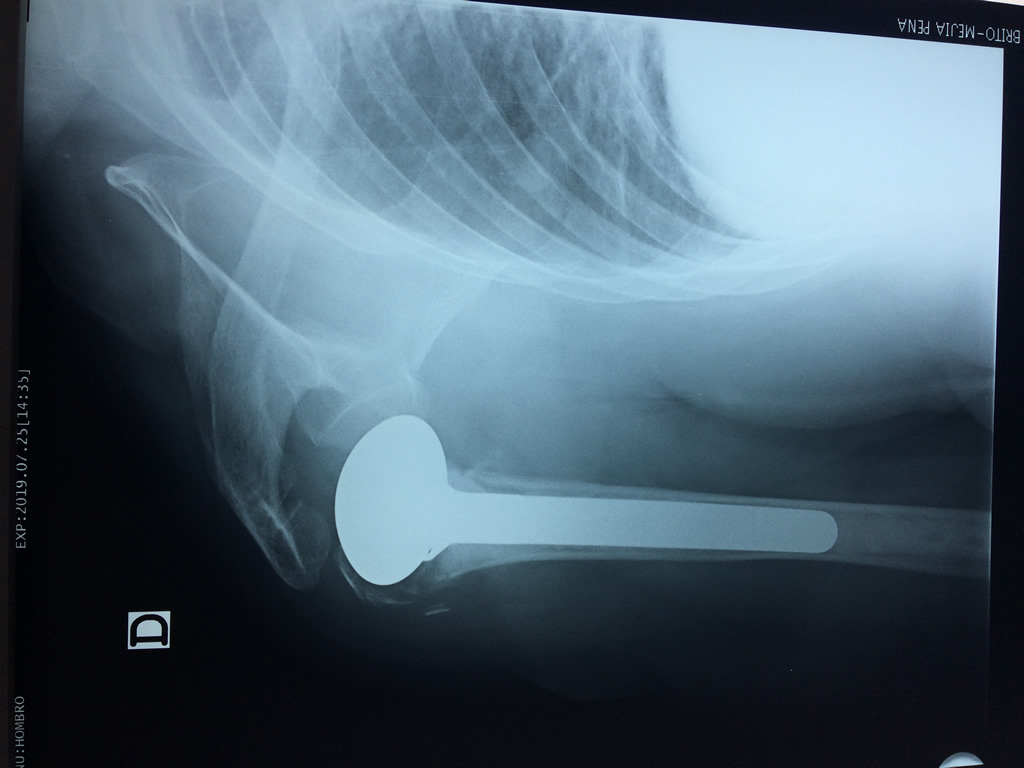

La principal articulación del hombro es la que une la cabeza del húmero con la escápula, recibe el nombre de articulación escapulohumeral y presenta dos superficies articulares, una de ellas corresponde a la cabeza del humero que tiene forma semiesférica y la otra es la cavidad glenoidea de la escápula, estas superficies están recubiertos por cartílago que permiten un movimiento suave e indoloro.